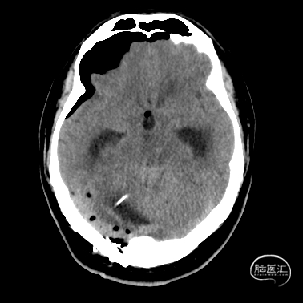

术后当天CT

术后1周CT复查